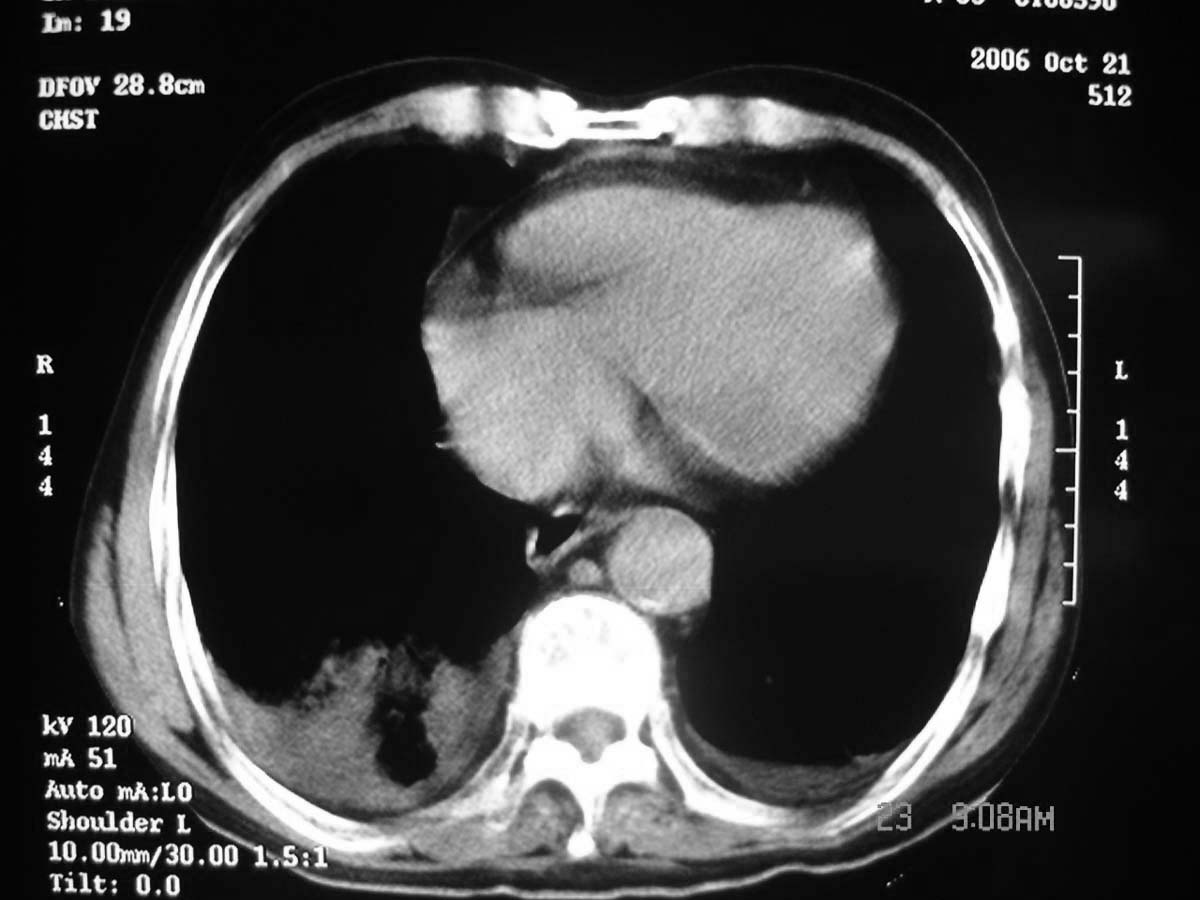

以下是引用守望可可西里在2006-11-23 14:33:00的发言:[br][br] 糖尿病病人很容易继发结核,病人又有双侧胸膜增厚、粘连、胸腔积液以及双上肺的斑片状、条索状影结核病灶影,以一元论考虑,右下肺病变首先考虑干酪性肺炎,可以正规抗炎治疗后复查,排除一般的肺炎。